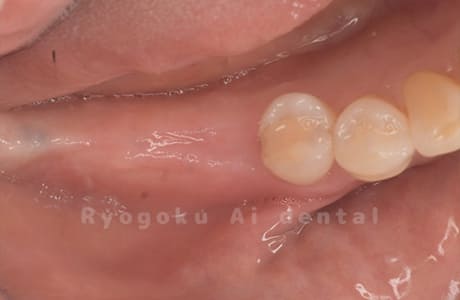

Case10

術前

-

術後

- 原因

- 左下6番欠損

- 治療内容

- インプラント治療

- 治療費用

- 約600,000円

左下の奥歯に歯を入れて欲しいとのことでご来院された患者様です。インプラント治療が最適とご提案させて頂き、治療を行いました。経過も良好で、大変満足して頂けました。

<リスク・副作用>

治療後、痛みや違和感、出血、腫れなどが出る事があります。喫煙者、糖尿病などの方の場合、歯が生着しない場合があります。